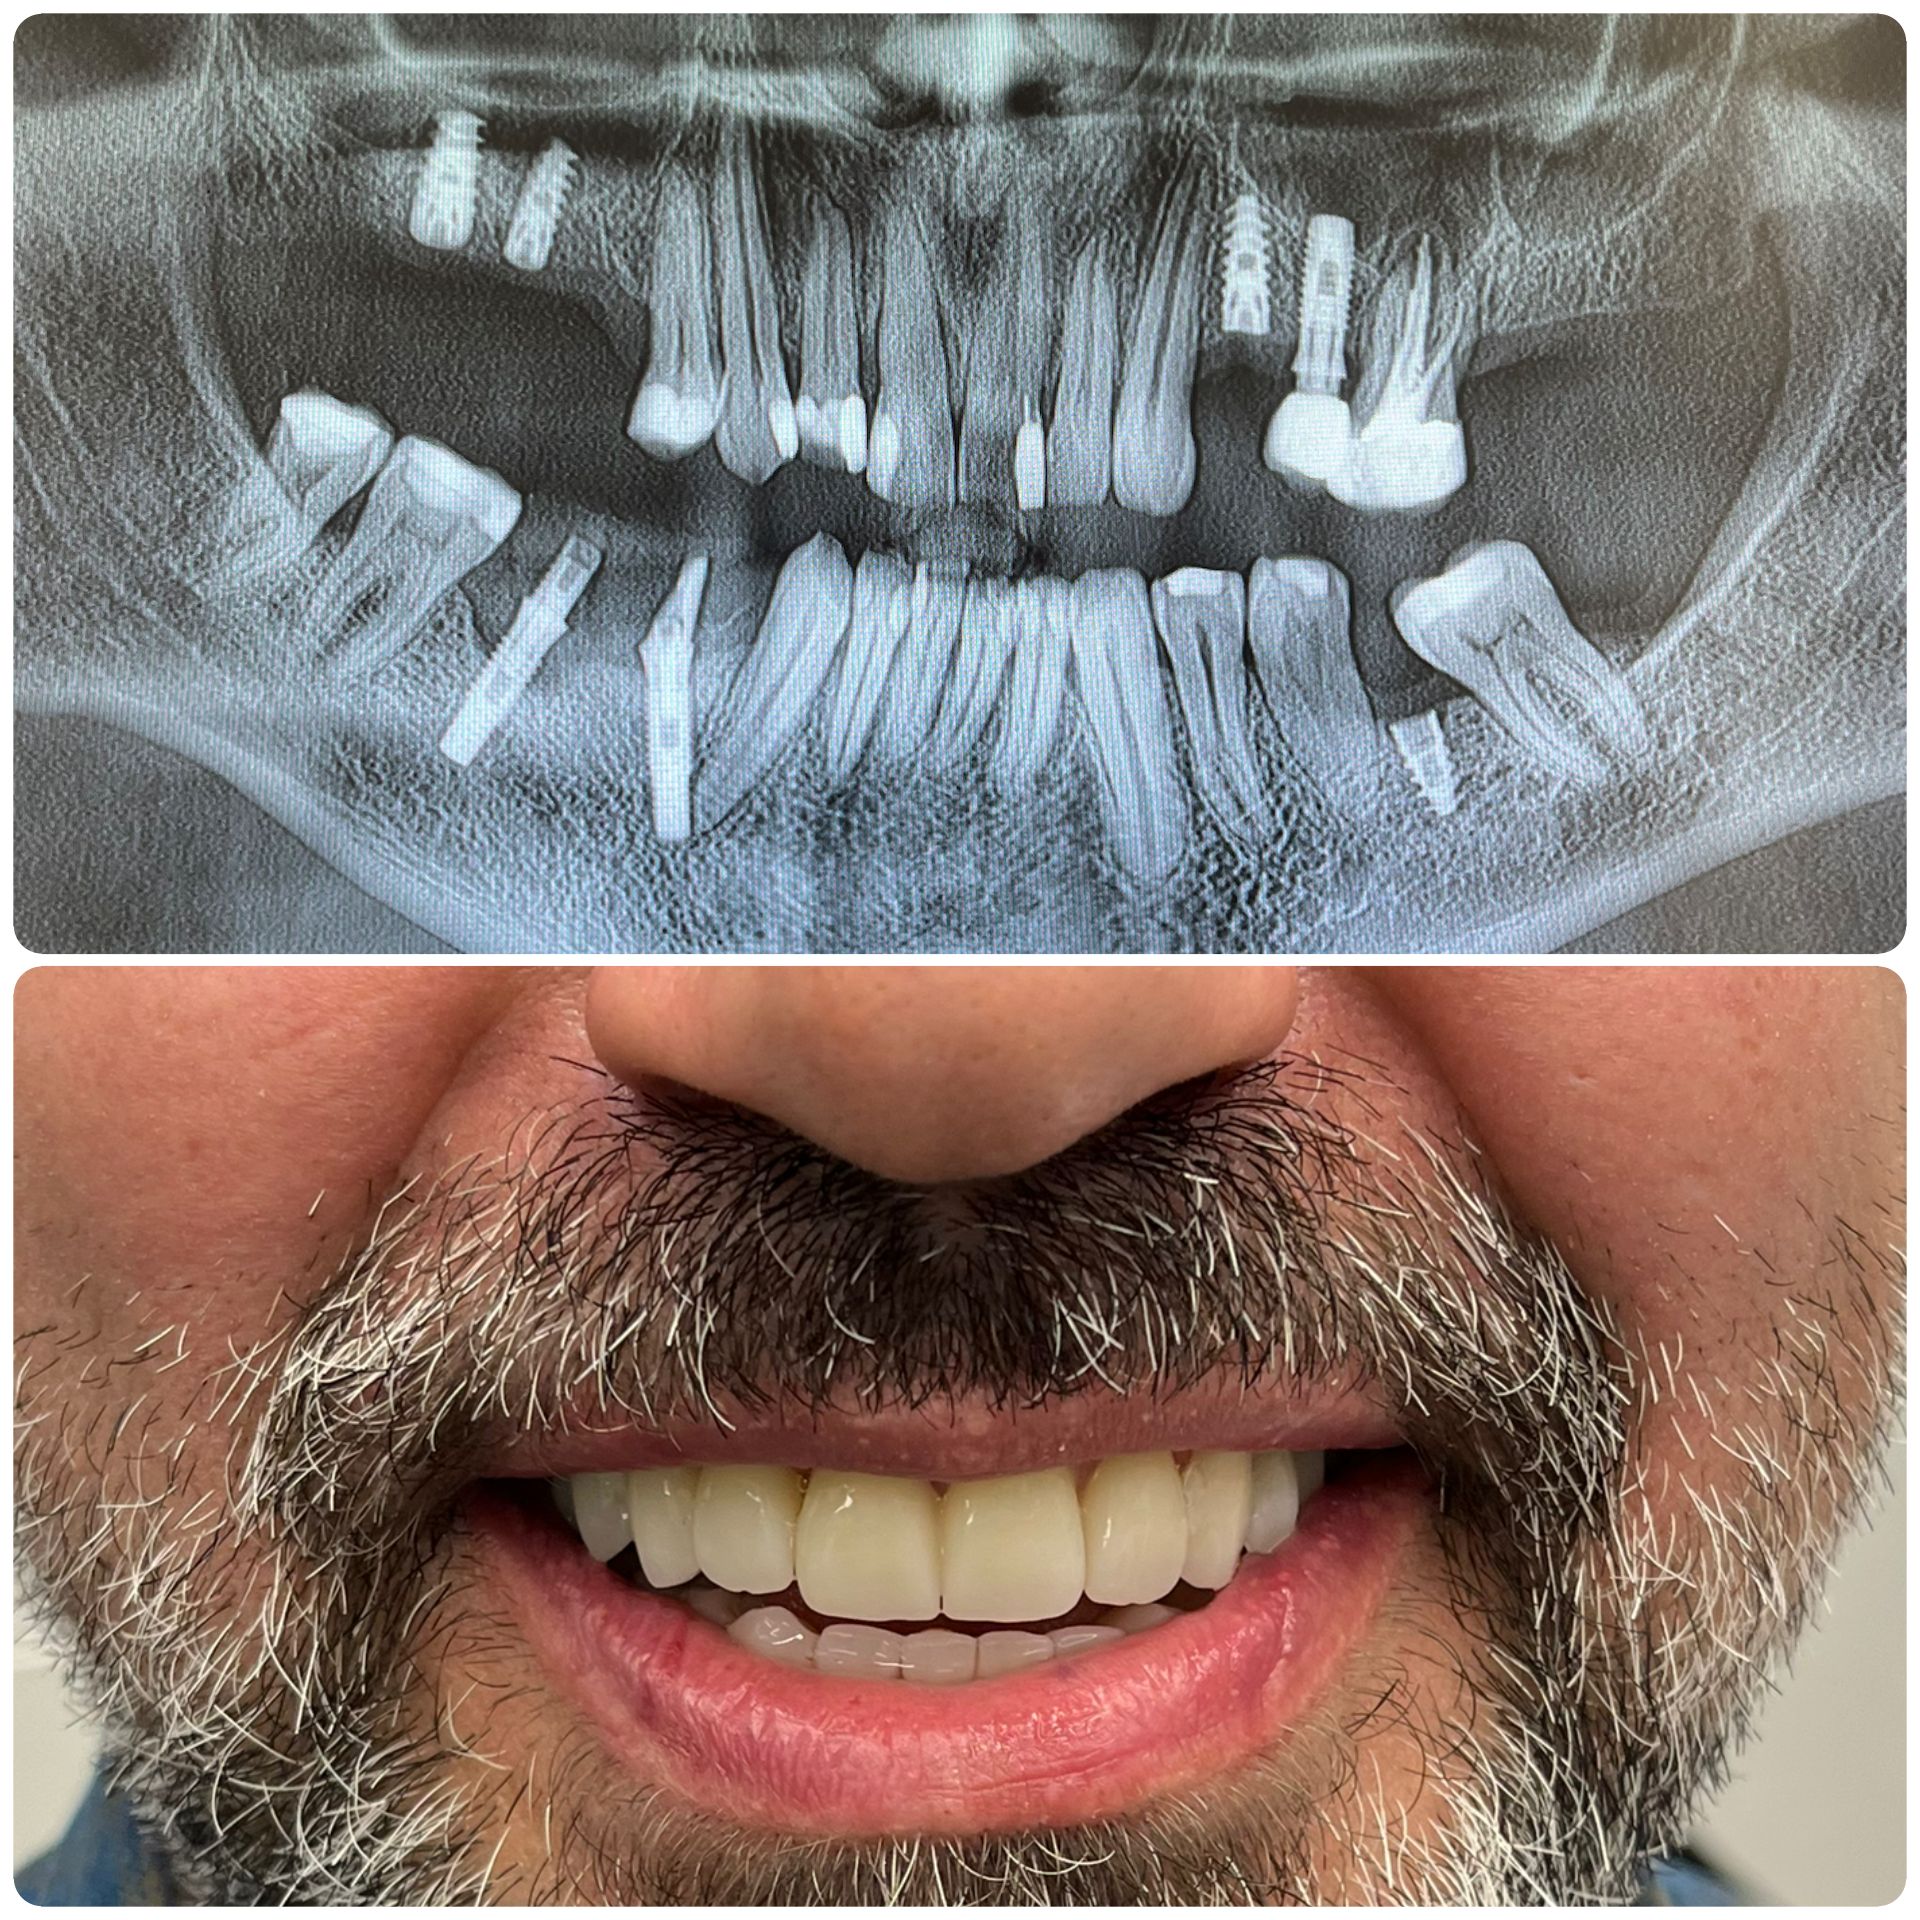

Si inizia con una consulenza e immagini 3D. Gli impianti vengono posizionati con precisione e restaurati con corone che appaiono e funzionano come denti naturali. L’intero processo è attentamente pianificato in fasi: valutazione, posizionamento dell’impianto, periodo di guarigione e restauro finale. Con le tecniche moderne, molte procedure sono minimamente invasive e spesso vengono fornite soluzioni temporanee, così da non rimanere mai senza sorriso durante il trattamento.

Con cure adeguate, gli impianti dentali possono durare tutta la vita, rappresentando uno dei migliori investimenti a lungo termine per la salute orale. Controlli regolari, buona igiene orale e uno stile di vita sano sono fondamentali per il successo degli impianti. Anche se la corona potrebbe dover essere sostituita dopo 10–15 anni a causa dell’usura normale, l’impianto in titanio è progettato per integrarsi con l’osso e rimanere stabile a vita.